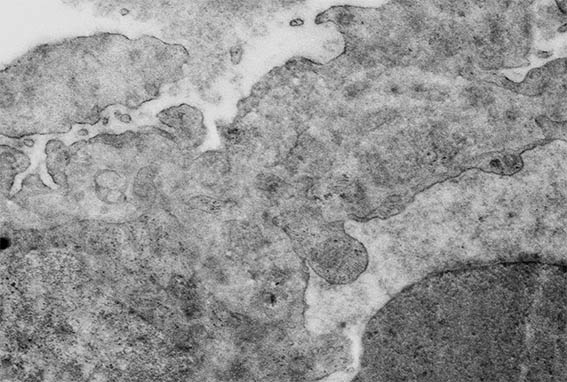

Figura 12. Microscopía electrónica, aumento original, X4.000. Daño segmentario de la pared capilar, con un doble contorno.